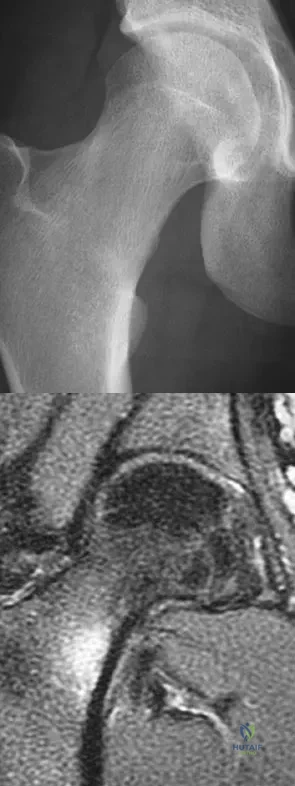

Question 11

A 21-year-old collegiate female cross-country athlete reports right hip pain that begins about 12 miles into a run, followed by pain resolution when she discontinues running. However, each time she tries to resume a running program, she experiences recurrence of pain deep in the anterior groin. A plain radiograph and MRI scan are shown in Figures 8a and 8b. Management should consist of

Explanation